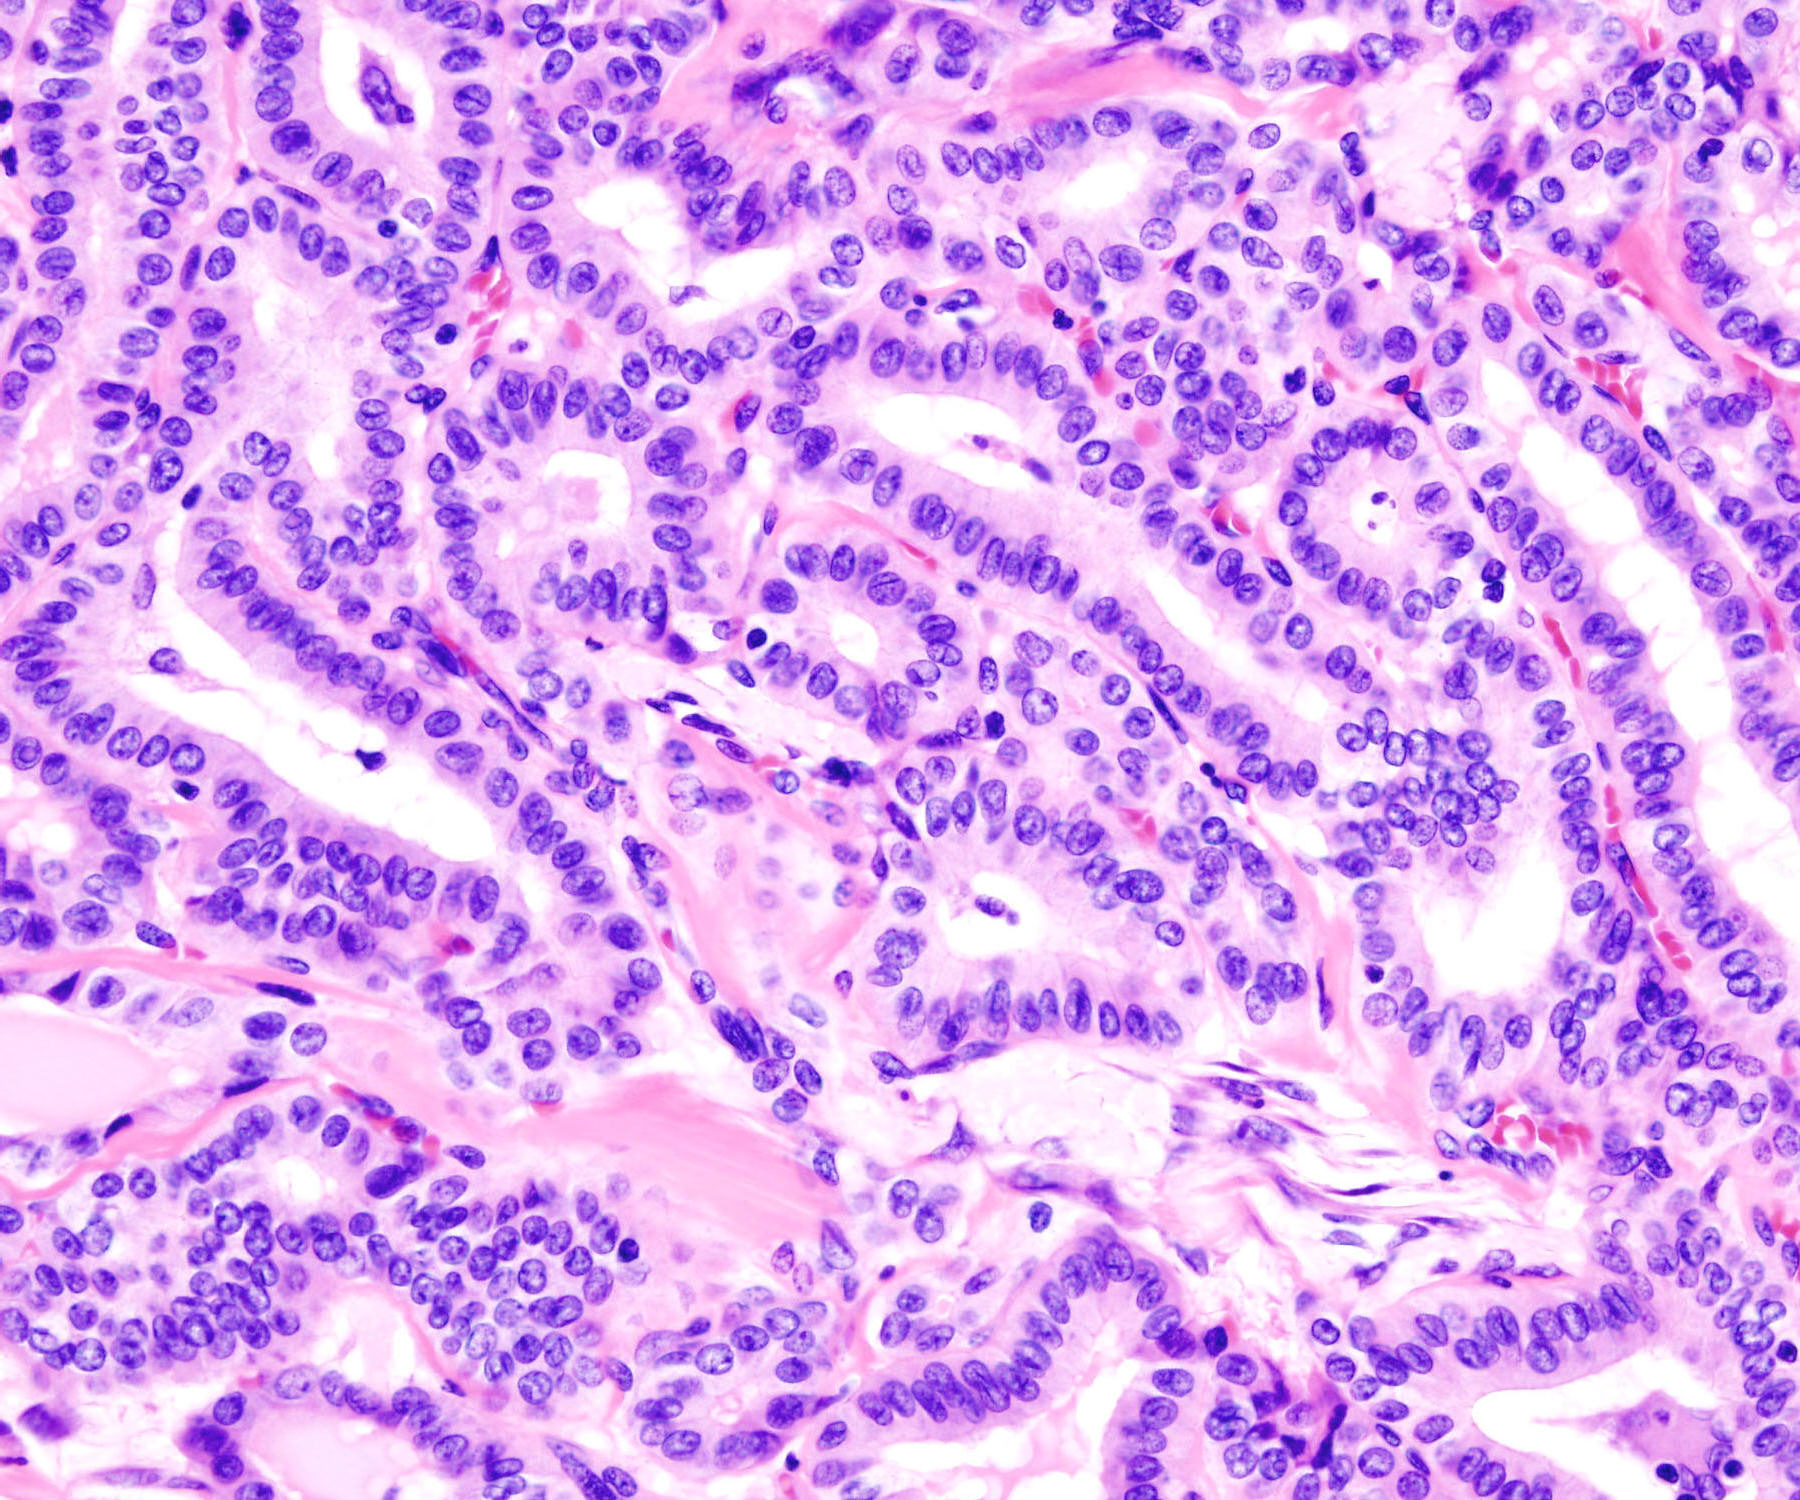

Source: Thyroid_papillary_carcinoma_histopatholgy_(2)